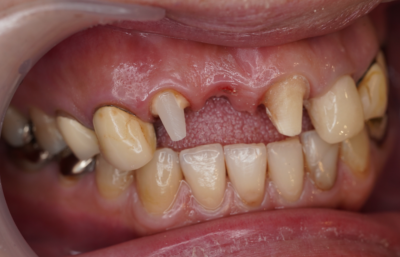

こちらの患者様は何年も前に入れた前歯の被せ物のレジンが欠けてご来院されました。

欠けた箇所のプラスチック修復を何度か繰り返していましたが頻繁に外れてしまうこともあり、新しい被せ物での修復を希望されました。

元々前歯は保険内での神経の治療と土台、被せ物での処置がされていましたが、今回は保険外の被せ物で審美的に綺麗に治したいというご希望がありました。

その為、中の土台を外して根管治療から修復させていただくことになりました。

※①②③のメタルコアを外して、ファイバーコアを築造していきます

※ブログ記事1番上の画像が③の歯の画像になります。